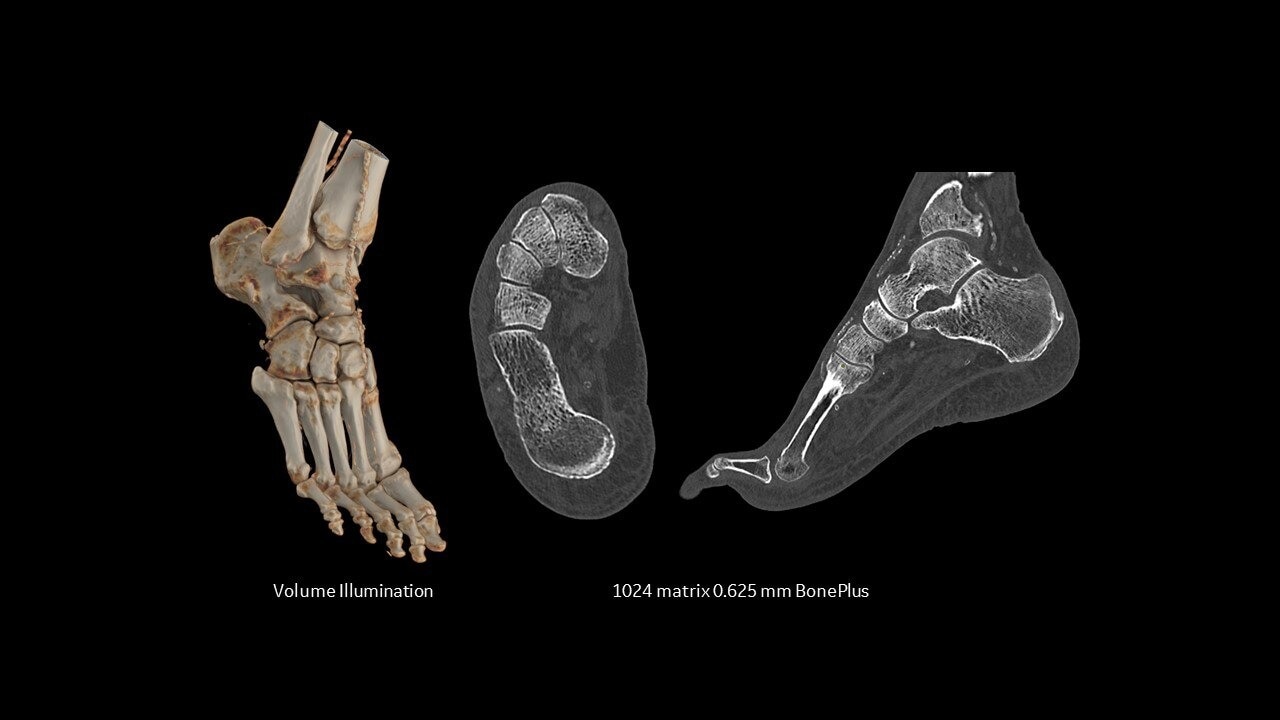

omni-legend-ct-ci-en

Your Omni Legend system can be updated and reliable for years to come

The highest sensitivity per cm in the market2 and scalability enable your PET/CT system to be optimized for both current and emerging tracers as well as for procedures beyond oncology such as cardiac and neuro imaging.